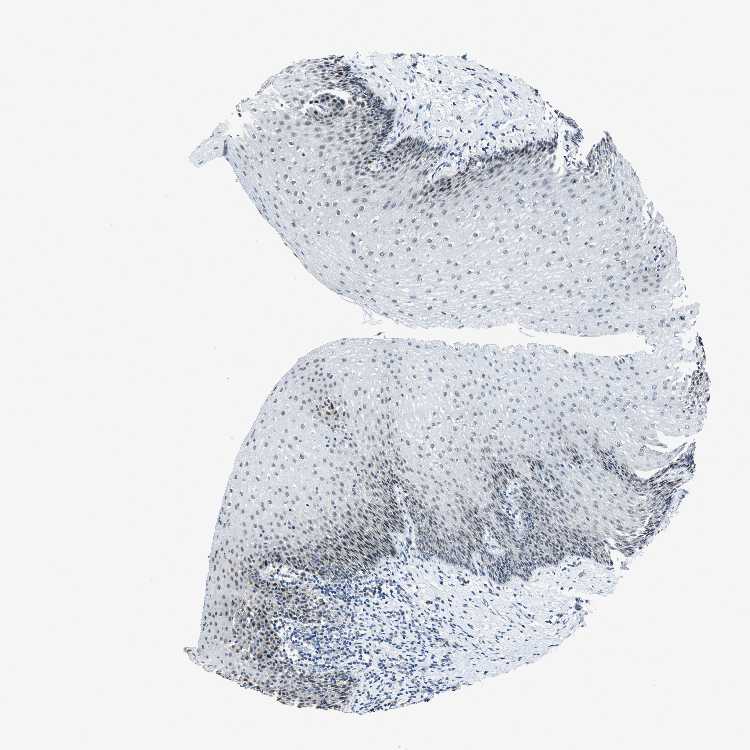

ESOPHAGUS - Antibody stainingi

Antibody staining in the annotated cell types in the current human tissue is reported as not detected, low, medium, or high, based on conventional immunohistochemistry profiling in selected tissues. This score is based on the combination of the staining intensity and fraction of stained cells.

Each image is clickable and will lead to virtual microscopy that enables deeper exploration of all samples and also displays staining intensity scores, fraction scores and subcellular localization as well as patient and tissue information for each sample.

Antibody HPA021501

Squamous epithelial cells Medium